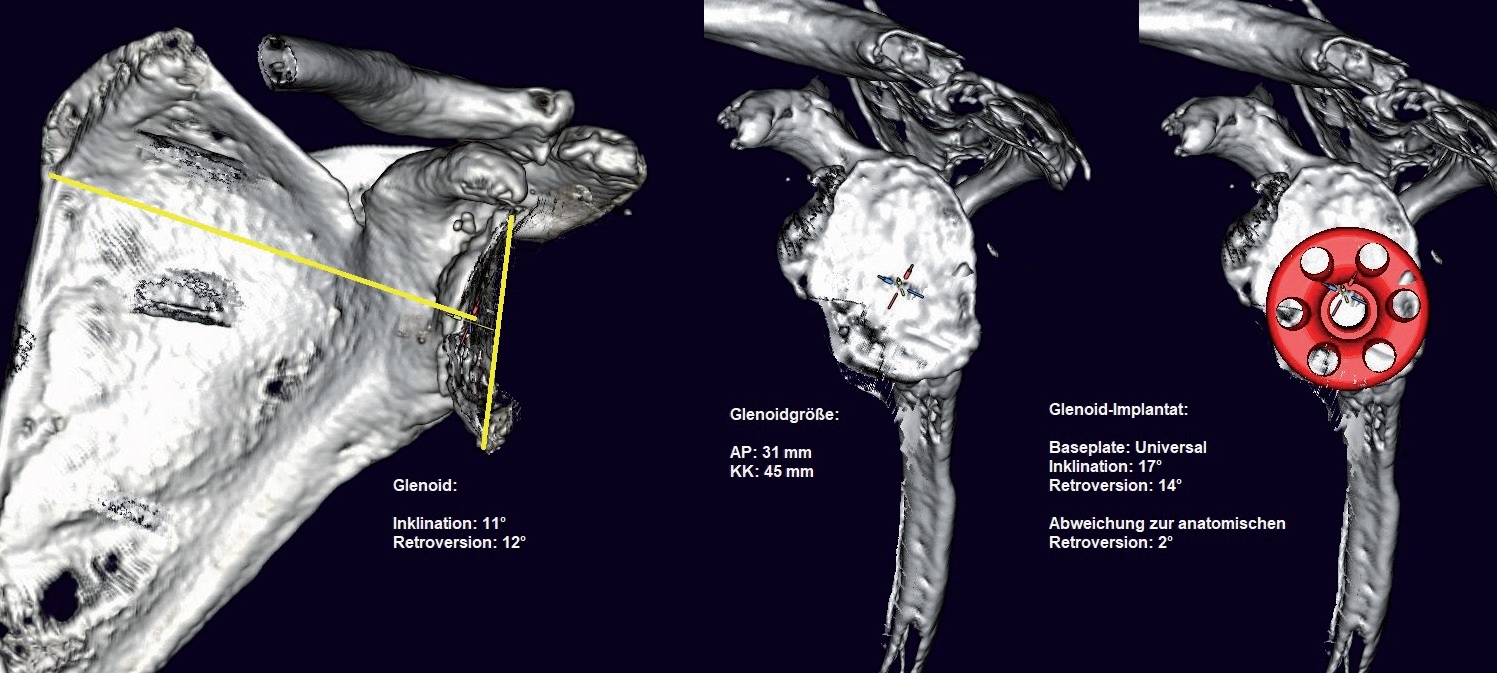

schneller. Ich brauche bspw. zwischen 5 und 10 Minuten für eine normale Schulterplanung. Für eine 3D-Planung

mit einer 3D-Gelenkrekonstruktion inklusive animierter 3D-ROM-Analyse und Betrachtung des Gelenkes aus verschiedenen

Blickwinkeln, so wie es aktuell mit der Software mediCAD® Shoulder 3D ermöglicht wird, brauche ich derzeit noch

Gerade das 3D-reponierte Gelenk, insbesondere bei der inversen Schulter TEP, mit sichtbarer implantierter Prothese

und Betrachtungsmöglichkeit aus jedem Blickwinkel im Raum, ist für mich derzeit noch etwas spannendes Neues mit

vielen noch möglichen Variablen. Derzeit versuche ich diese spielerisch herauszufinden, um die bisher bekannte optimale

Prothesenposition zu finden, anhand neuer Möglichkeiten zu überprüfen und zu validieren, idealerweise unter Berücksichtigung

von Weichteil-Spannungsverhältnissen durch Längenveränderungen. Anfangs habe ich für die gleichen

Weiterer Vorteil von von mediCAD® Shoulder 3D ist, dass der Operateur mit der Software selbst (und nicht irgendein

Ingenieur des Implantatherstellers) die Segmentierung des CT-Datensatzes durchführen kann, entsprechend seiner medizinischen

Erfahrung und Interpretation der CT Bilder. Außerdem sind das Erstellen eines 3D-Modells und die Möglichkeit

der anschließende Planung von Glenoid und Humerus einzeln hintereinander möglich. Auch die vollständige

Gelenkplanung nach der Reposition des Gelenkes mit implantierten Komponenten sind Funktionen, die ich als Arzt nicht

missen möchte. Und natürlich die 3D-ROM-Analyse des reponierten Gelenkes bei innenliegender Prothese.